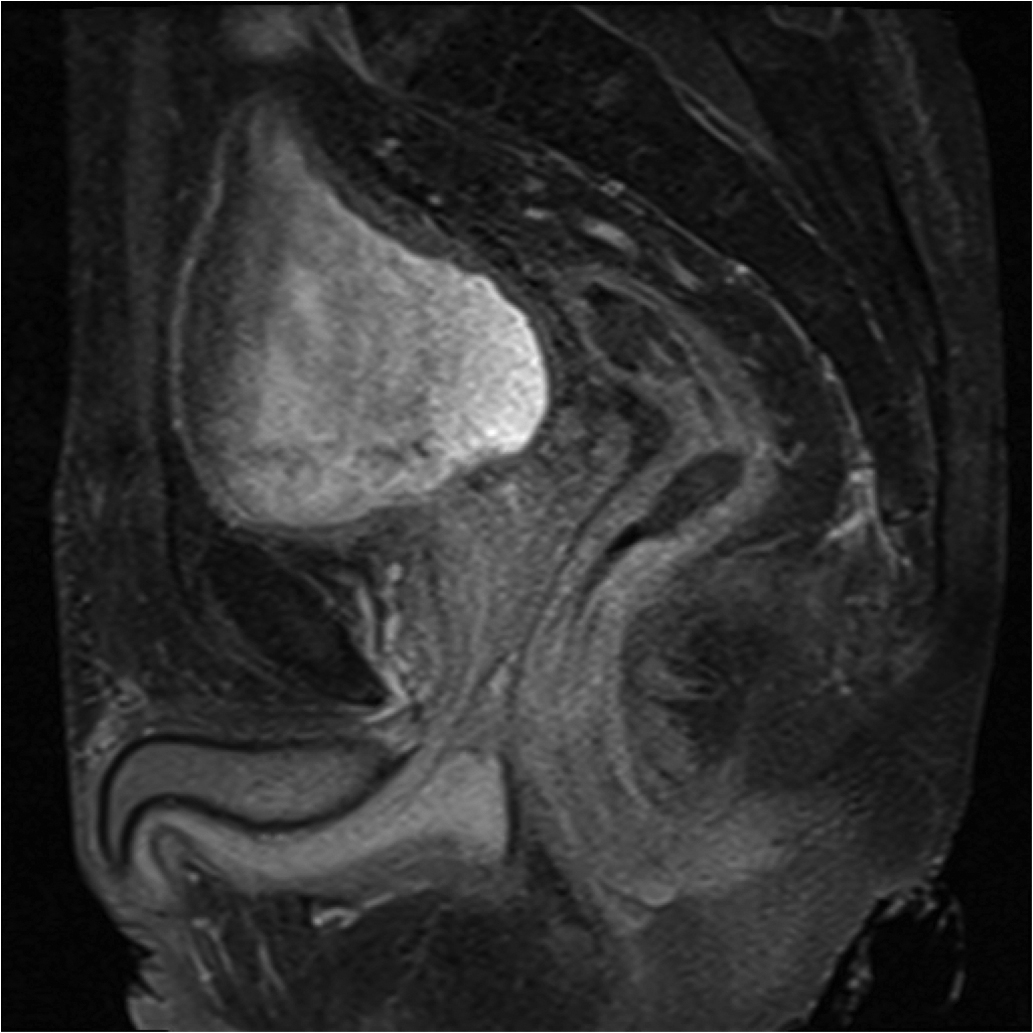

Fig1. Pacient cu neoplasm rectal stadiul IIIC (T3; N2; M0) confirmat bioptic, adenocarcinom mixt G2

a-d imagini T2 ponderate în plan sagital, oblic axial și oblic coronal – masă tisulară dezvoltată superior de joncțiunea anorectală, lateral dreapta, cu minimă extensie la nivelul grăsimii mezorectale și limfoganglioni mezorectali cu diametru de până la 10 mm;

Fig.2. Același pacient post chimio-/ radioterapie – răspuns complet cu dispariția masei tumorale rectale; dispariția restricției de difuzie și reducere în dimensiuni a ganglionilor mezorectali; pacientul a beneficiat de TME şi s-a confirmat histopatologic absenţa ţesutului tumoral (pT0 pN0).

a-d) imagini T2 ponderate în 3 planuri

f) sagital T1 postcontrast